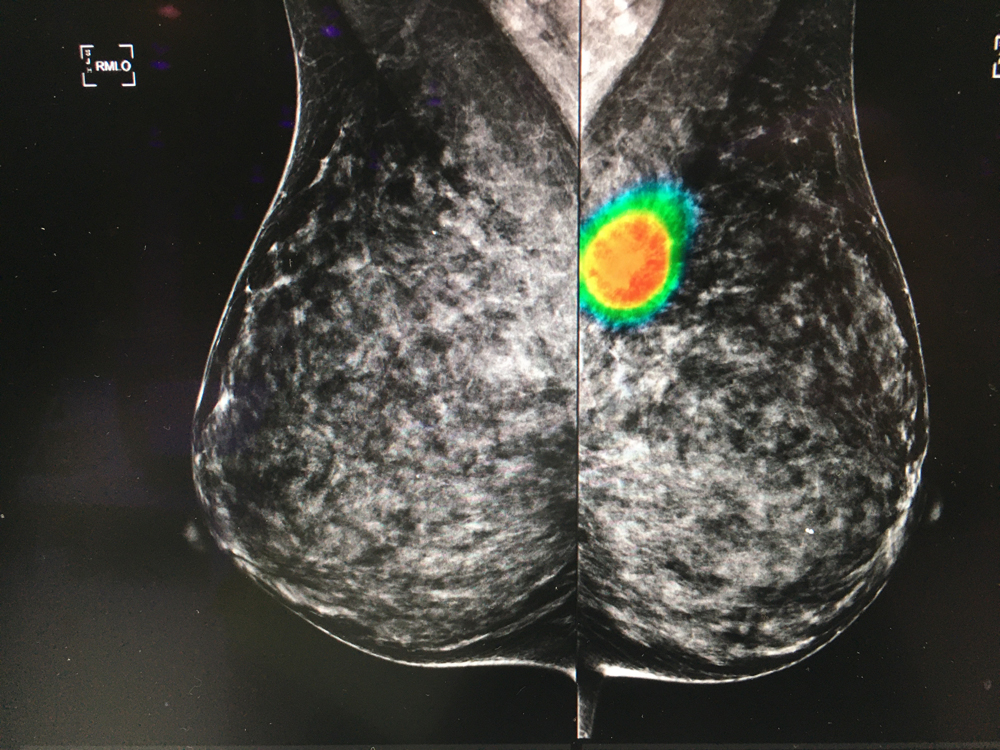

Here are images of some of the newest new medical imaging technologies displayed on the expo floor at the Radiological Society of North America (RSNA) 2019 meeting. Use the slider images below to see the photos.